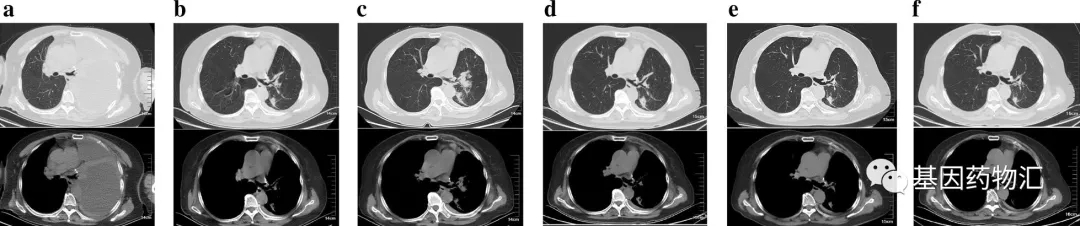

按照经验来说,Ⅲ期肺癌的治愈率也能有20%~30%,当然前提是患者按照规范进行术后的辅助治疗,并且按时复查、及时判断复发的情况。但这位患者拒绝了所有的辅助治疗,并且拒不复查,导致错失了治疗良机,直到3年多以后的2019年6月,她再因呼吸困难就诊的时候,再次被诊断为Ⅳ期的肺腺癌(下图a,可见大量胸腔积液;图b为胸腔穿刺后影像,可见左下叶2病灶)。

但最终,治疗效果不是很理想。接受治疗2个月后复查胸部CT时,患者的病灶仍在变大(图c),提示疾病持续进展。医生考虑为患者更换方案。

机缘巧合,使用拉罗替尼的机会来了。这一次,患者用上了针对她NCOR2-NTRK1融合突变的靶向治疗药物,TRK抑制剂拉罗替尼。用药仅1个月,复查时CT扫描(图d)就显示病灶体积缩小了30%,达到了部分缓解!

疗效良好,患者继续治疗。又2个月之后的检查结果显示(图e),患者的病灶体积缩小50%,且还在持续缩小,没有新发的转移病灶。至用药半年(图f),一部分病灶彻底消失。截至2020年12月,患者已经持续治疗超过15个月!

图a为患者2019年6月诊断时的CT影像,可见大量胸腔积液;图b为患者胸腔穿刺后的影响,排除胸腔积液干扰后,发现左下叶有2个转移性结节;图c为患者接受PD-1抑制剂卡瑞利珠单抗治疗2个周期后的影像,病灶仍在增大;图d为患者应用拉罗替尼治疗1个月后的影像,部分病灶开始缩小;图e为患者接受拉罗替尼治疗3个月后的影像,部分病灶不断缩小;图f为患者接受拉罗替尼治疗6个月后的影像,部分病灶缩小,甚至消失。